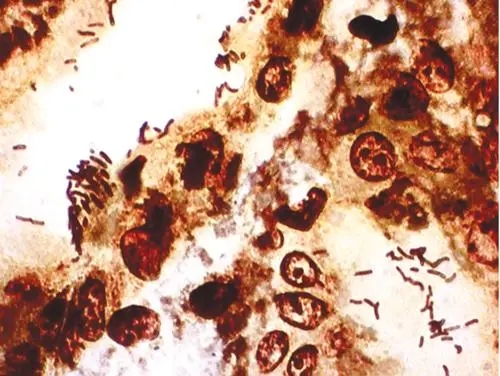

过碘酸-雪夫(Pexiodic acid-schiff,PAS)染色又称糖原染色。胞浆内存在的糖原或多糖类物质(如黏多糖、黏蛋白、糖蛋白、糖酯等)中的乙二醇基(CHOH-CHOH)经过碘酸(Periodic acid)氧化,转变为二醛基(CHO-CHO),与雪夫(Schiff

过碘酸-雪夫(Pexiodic acid-schiff,PAS)染色又称糖原染色。胞浆内存在的糖原或多糖类物质(如黏多糖、黏蛋白、糖蛋白、糖酯等)中的乙二醇基(CHOH-CHOH)经过碘酸(Periodic acid)氧化,转变为二醛基(CHO-CHO),与雪夫(Schiff)试剂中的无色品红结合,形成紫红色化合物而沉积于胞浆中糖原类物质所存在的部位。该反应称为过碘酸-雪夫(PAS)阳性反应。